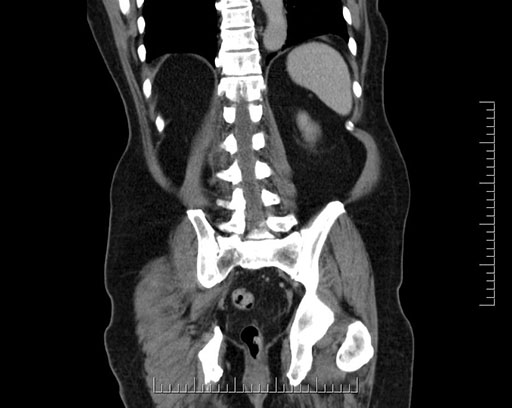

Imaging Analysis

Look through the patient's CT scan to identify any areas of concern for the necessary procedure.

Based on your CT findings, which issue(s) would give reason for "planned slowing down moment(s)" in this case?